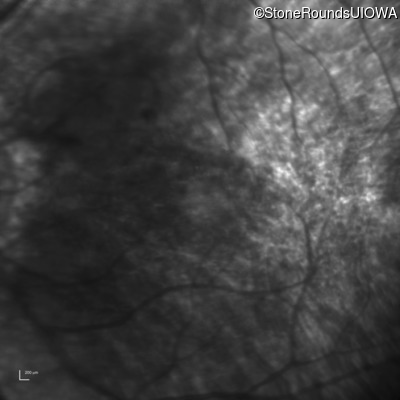

Age at visit: 17 years

This 17 year old female feels that the vision in her right eye has worsened since her cataract surgery 8 weeks ago.